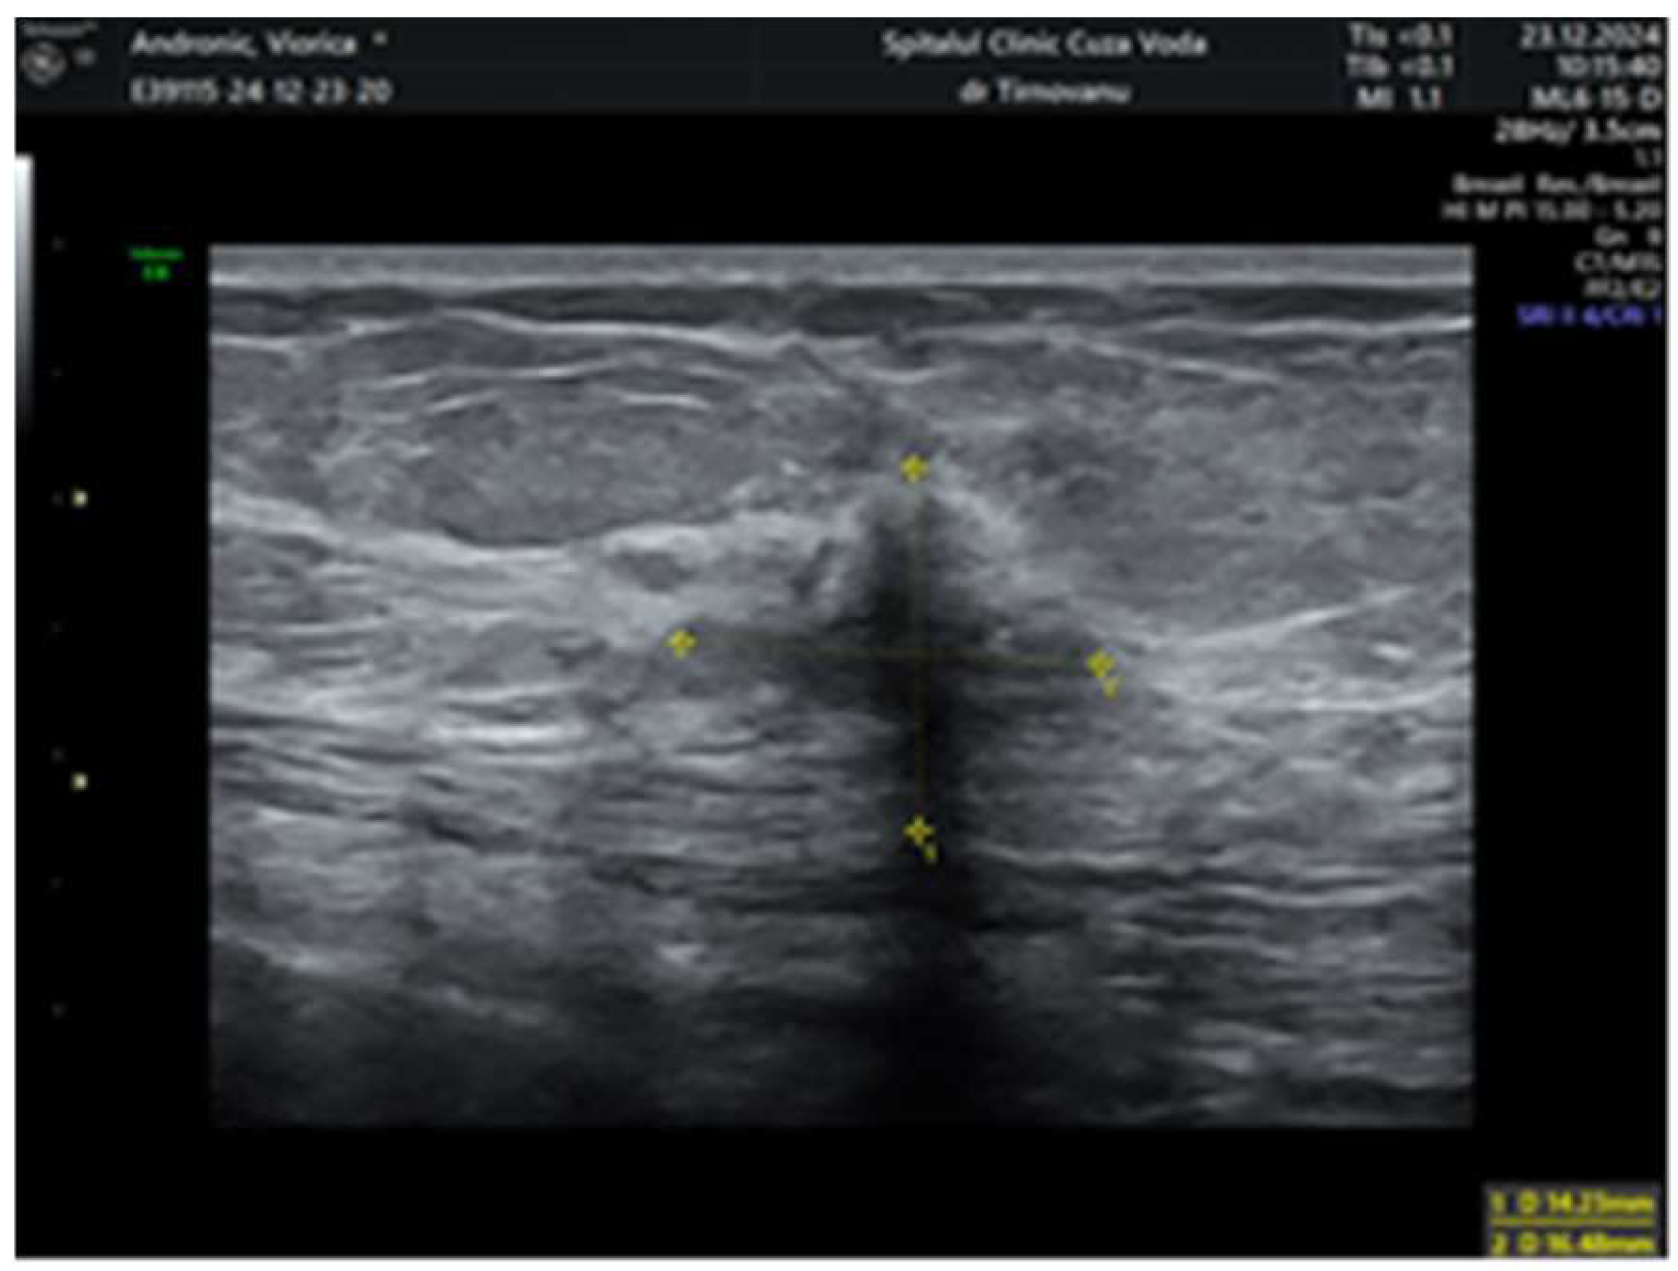

2. Case Report